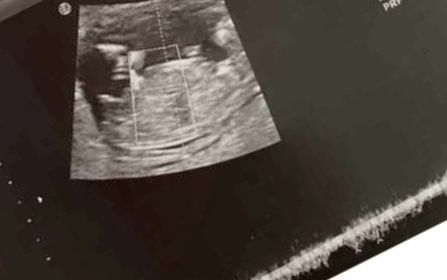

Scusate forse è stupida come domanda ma.. L'altro gg ho fatto l'ecografia 10 settimane, tutto benissimo fortunatamente, l'unica cosa che poi mi è sembrata strana è che il mio pulcino è sù(posizionato in alto) come se stesse a pancia in giù, non so se...